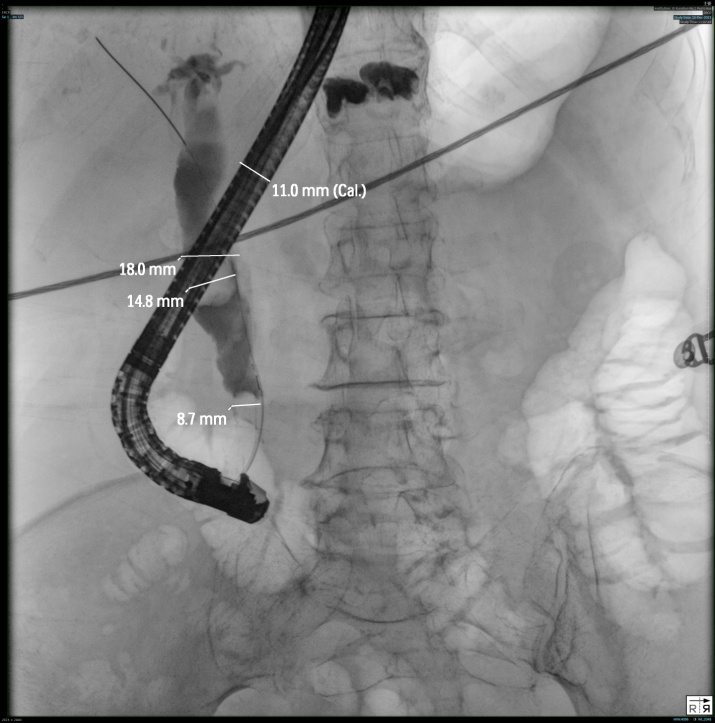

12月16日,王庆华主任团队为王阿姨紧急实施“经内镜逆行性胰胆管造影术(ERCP)+胆道减压+胆道支架植入”术,如头发丝般粗细的导丝引导着乳头切开刀进入胆总管,成功置入胆管支架后,黑褐色的脓性胆汁大量流出,堵塞了几天的胆总管终于通畅了!接下来,经过抗感染治疗,王阿姨的腹痛、发热、黄疸等症状得以逐步缓解,转入肝胆外科进一步诊治。

▲ERCP手术

▲胆道支架置入